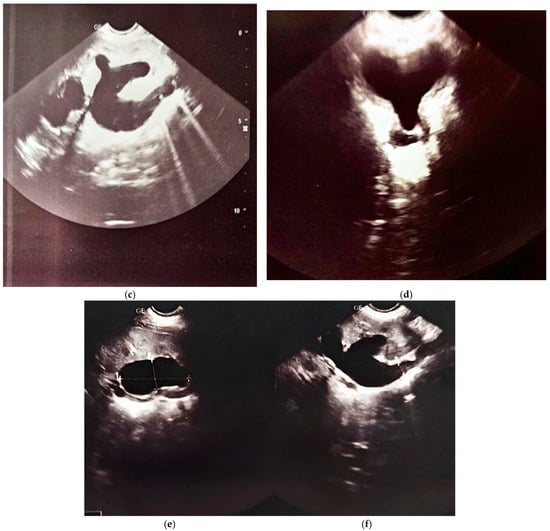

At 18 months of life, the child was rehospitalized for surgical reevaluation. Under general anesthesia, exploratory cystoscopy (Figure 3b) revealed that the bladder mucosa exhibited a “fighting bladder” appearance with pseudopolypoid and pseudodiverticular changes. The distal ends of the Cook catheters were observed at the ureteral orifices. The Cook catheters were removed with favorable postoperative evolution (Figure 4).

Figure 4.

Renal scintigraphy at two months of life.

Over the course of these seven years, four renal scintigraphies were conducted. The first procedure took place when the child was just two months old. The first renal scintigraphy was performed using 99M TC–DTPA. The results indicated that the left kidney was in a normal position, slightly hypertrophic, with irregular contours, normal perfusion, and homogenous parenchymal uptake. The glomerular filtration rate (GFR) was 91.2 mL/min. Spontaneous excretion was observed, with transient lower ureteral dilation but no evidence of stasis in the excretory pathways by the end of the study. The renogram showed a normal peak at 2 min with a descending excretory slope, slightly elevated T1/2, and activity retention (AR). A non-obstructive response to furosemide was noted.

The right kidney was in a normal position but reduced in size, showing reduced perfusion with delayed peak uptake, heterogeneous parenchymal distribution, and a GFR of 9.4 mL/min. Excretion was spontaneous but reduced and slow, without evidence of obstruction or stasis in the excretory pathways by the end of the study. The renogram revealed a flattened peak with reduced amplitude at 4 min and a slowly ascending excretory segment with delayed T1/2 and increased residual activity at 20 min. A non-obstructive response to furosemide was also observed.

The differential functional contribution was 86% for the left kidney and 14% for the right kidney, with a total GFR of 100.6 mL/min. The conclusion was that the right kidney was hypoplastic with significantly diminished function (Figure 5).